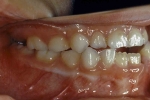

| 初診時